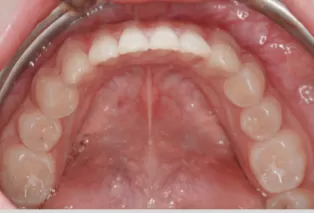

Intraoral photos

Intraoral photos after treatment